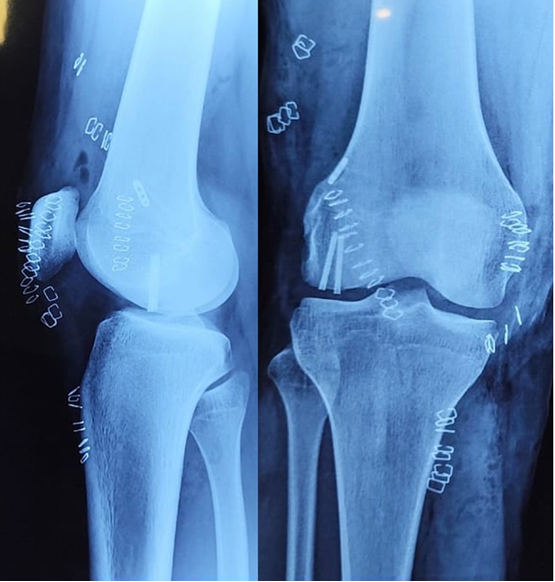

Final tightening of the MPFL graft was done by pulling the tensioning threads. A confirmatory shoot was taken through the fluoroscopy machine to confirm the fragment reduction and the position of the Herbert screws. Fig. 9.

The lateral arthrotomy was closed with absorbable Number 1 Polyglactin 910 suture to ensure a watertight closure. The subcutaneous tissue was closed with 2-0 Polyglactin 910 sutures. Skin was closed with skin staplers. Fig. 10.

Figure 10: Immediate post-operative radiographs of the right knee.

The patient was given a compression dressing and a long knee brace post-surgery for the post-operative period. The patient was advised to start knee range of movement exercises from the following day to allow for the lateral arthrotomy not to fibrose and cause excessive lateral tightness. He was advised 4 weeks of non-weight bearing with a walker/crutch and was advised to switch to partial weight bearing after 4 weeks post-surgery. The patient was followed up at 4 weeks to start partial weight bearing and a regular follow-up. He had achieved ROM up to 90° but had developed a 10° flexion deformity. He was advised aggressive physiotherapy, prone extensions, and quadriceps strengthening. He followed up at 6 months with full extension achieved and a range from 0°to 120°. He was still complaining of pain on and off, but had resumed all activities, including playing racquet sports regularly. There were no episodes or any feeling of patellar instability. The osteochondral fragment was holding well and had achieved radiological union. The patient was advised to follow-up at 1 year. Fig. 11.

Figure 11: 6 months follow-up X-ray of the right knee showing healing of the fragment.